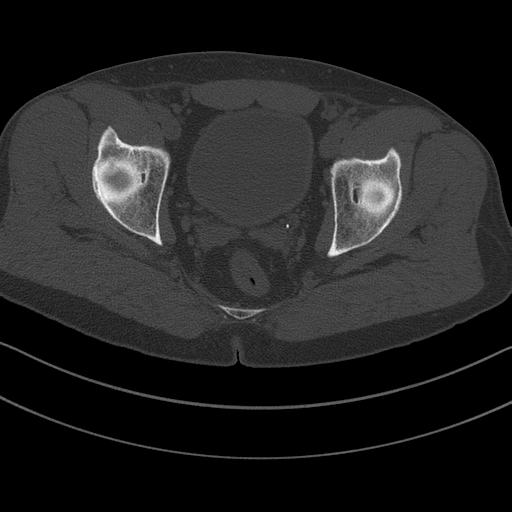

Gãy ổ cối (Acetabular fracture)